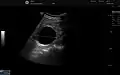

Simple renal cyst.jpg

Simple renal cyst